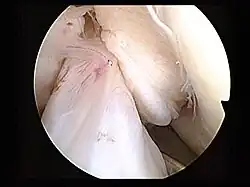

Arthroskopie

Der eigentliche Eingriff beginnt mit der Einführung des Arthroskops in das Knie des Patienten. Die Diagnose »Kreuzbandriss« kann so nochmals bestätigt werden. Andere Verletzungen, insbesondere des Meniskus, können vor der Rekonstruktion des Kreuzbandes versorgt werden.